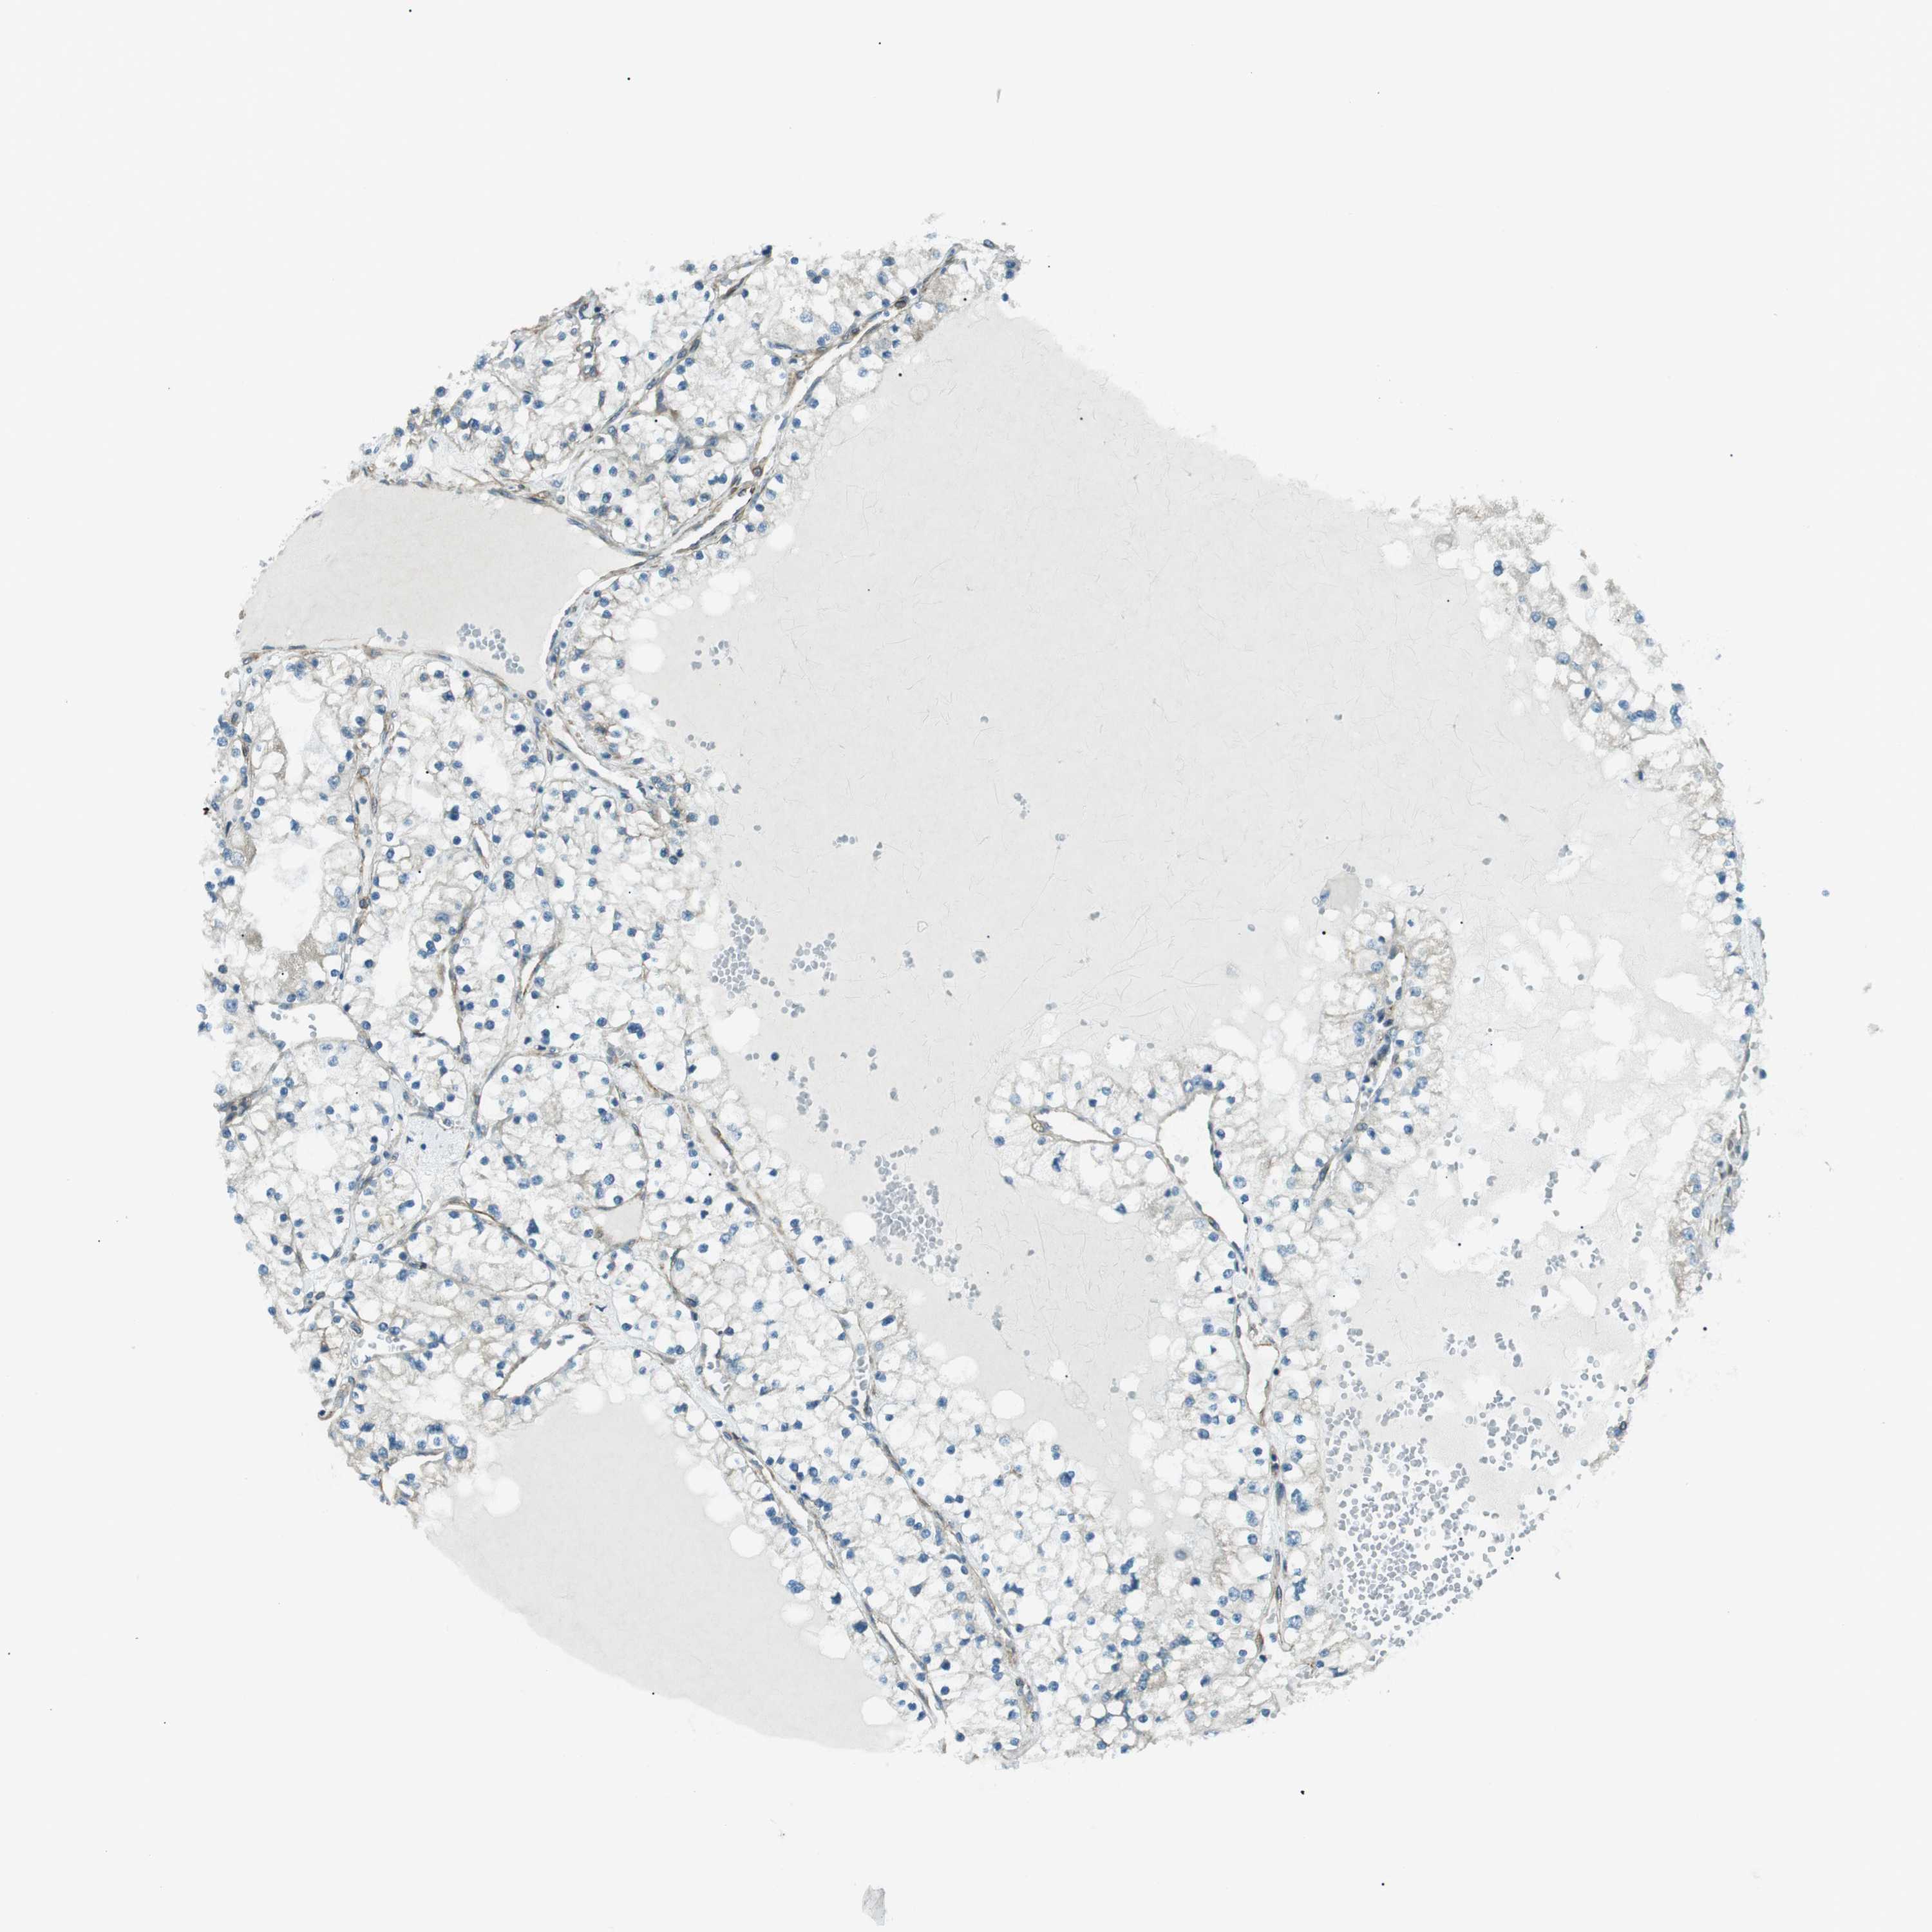

CANCER RENAL CANCER Show tissue menu

KICH TCGA KIRC TCGA KIRC VALIDATION KIRP TCGA PROTEIN RCC CPTAC PROTEIN EXPRESSION